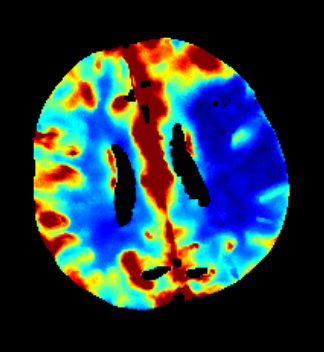

Furthermore mRay is capable of performing image processing tasks such as finding, visualizing and quantifying anomalies in tissue. In particular the image analysis module mRay VEOcore may be used to perform an automated processing of brain images from imaging modalities such as CT, CT-Perfusion, or MRI including a Diffusion Weighted Imaging (DWI) Module. As a result, changes in contrast over time are visualized as colored perfusion maps, including flow related parameters and tissue blood volume quantification.

The perfusion analysis of brain imaging data visualizes and quantifies tissue that is less supplied with blood (penumbra), oxygen deprived tissue caused by obstructed blood flow (core tissue) and the mismatch ratio between the two. The calculated values can be used to support decision making based on an assessment of the extent of tissue damage.

16.1. Overview

VEOcore is a fully automated image processing tool to calculate quantitative measures of affected brain tissue and healthy tissue. Therefore, this manual covers the instructions on how to interpret the results. It’s an extension the mRay Server application and the results can be viewed inside the mRay Client. Furthermore processed results can be automatically forwarded to the PACS.